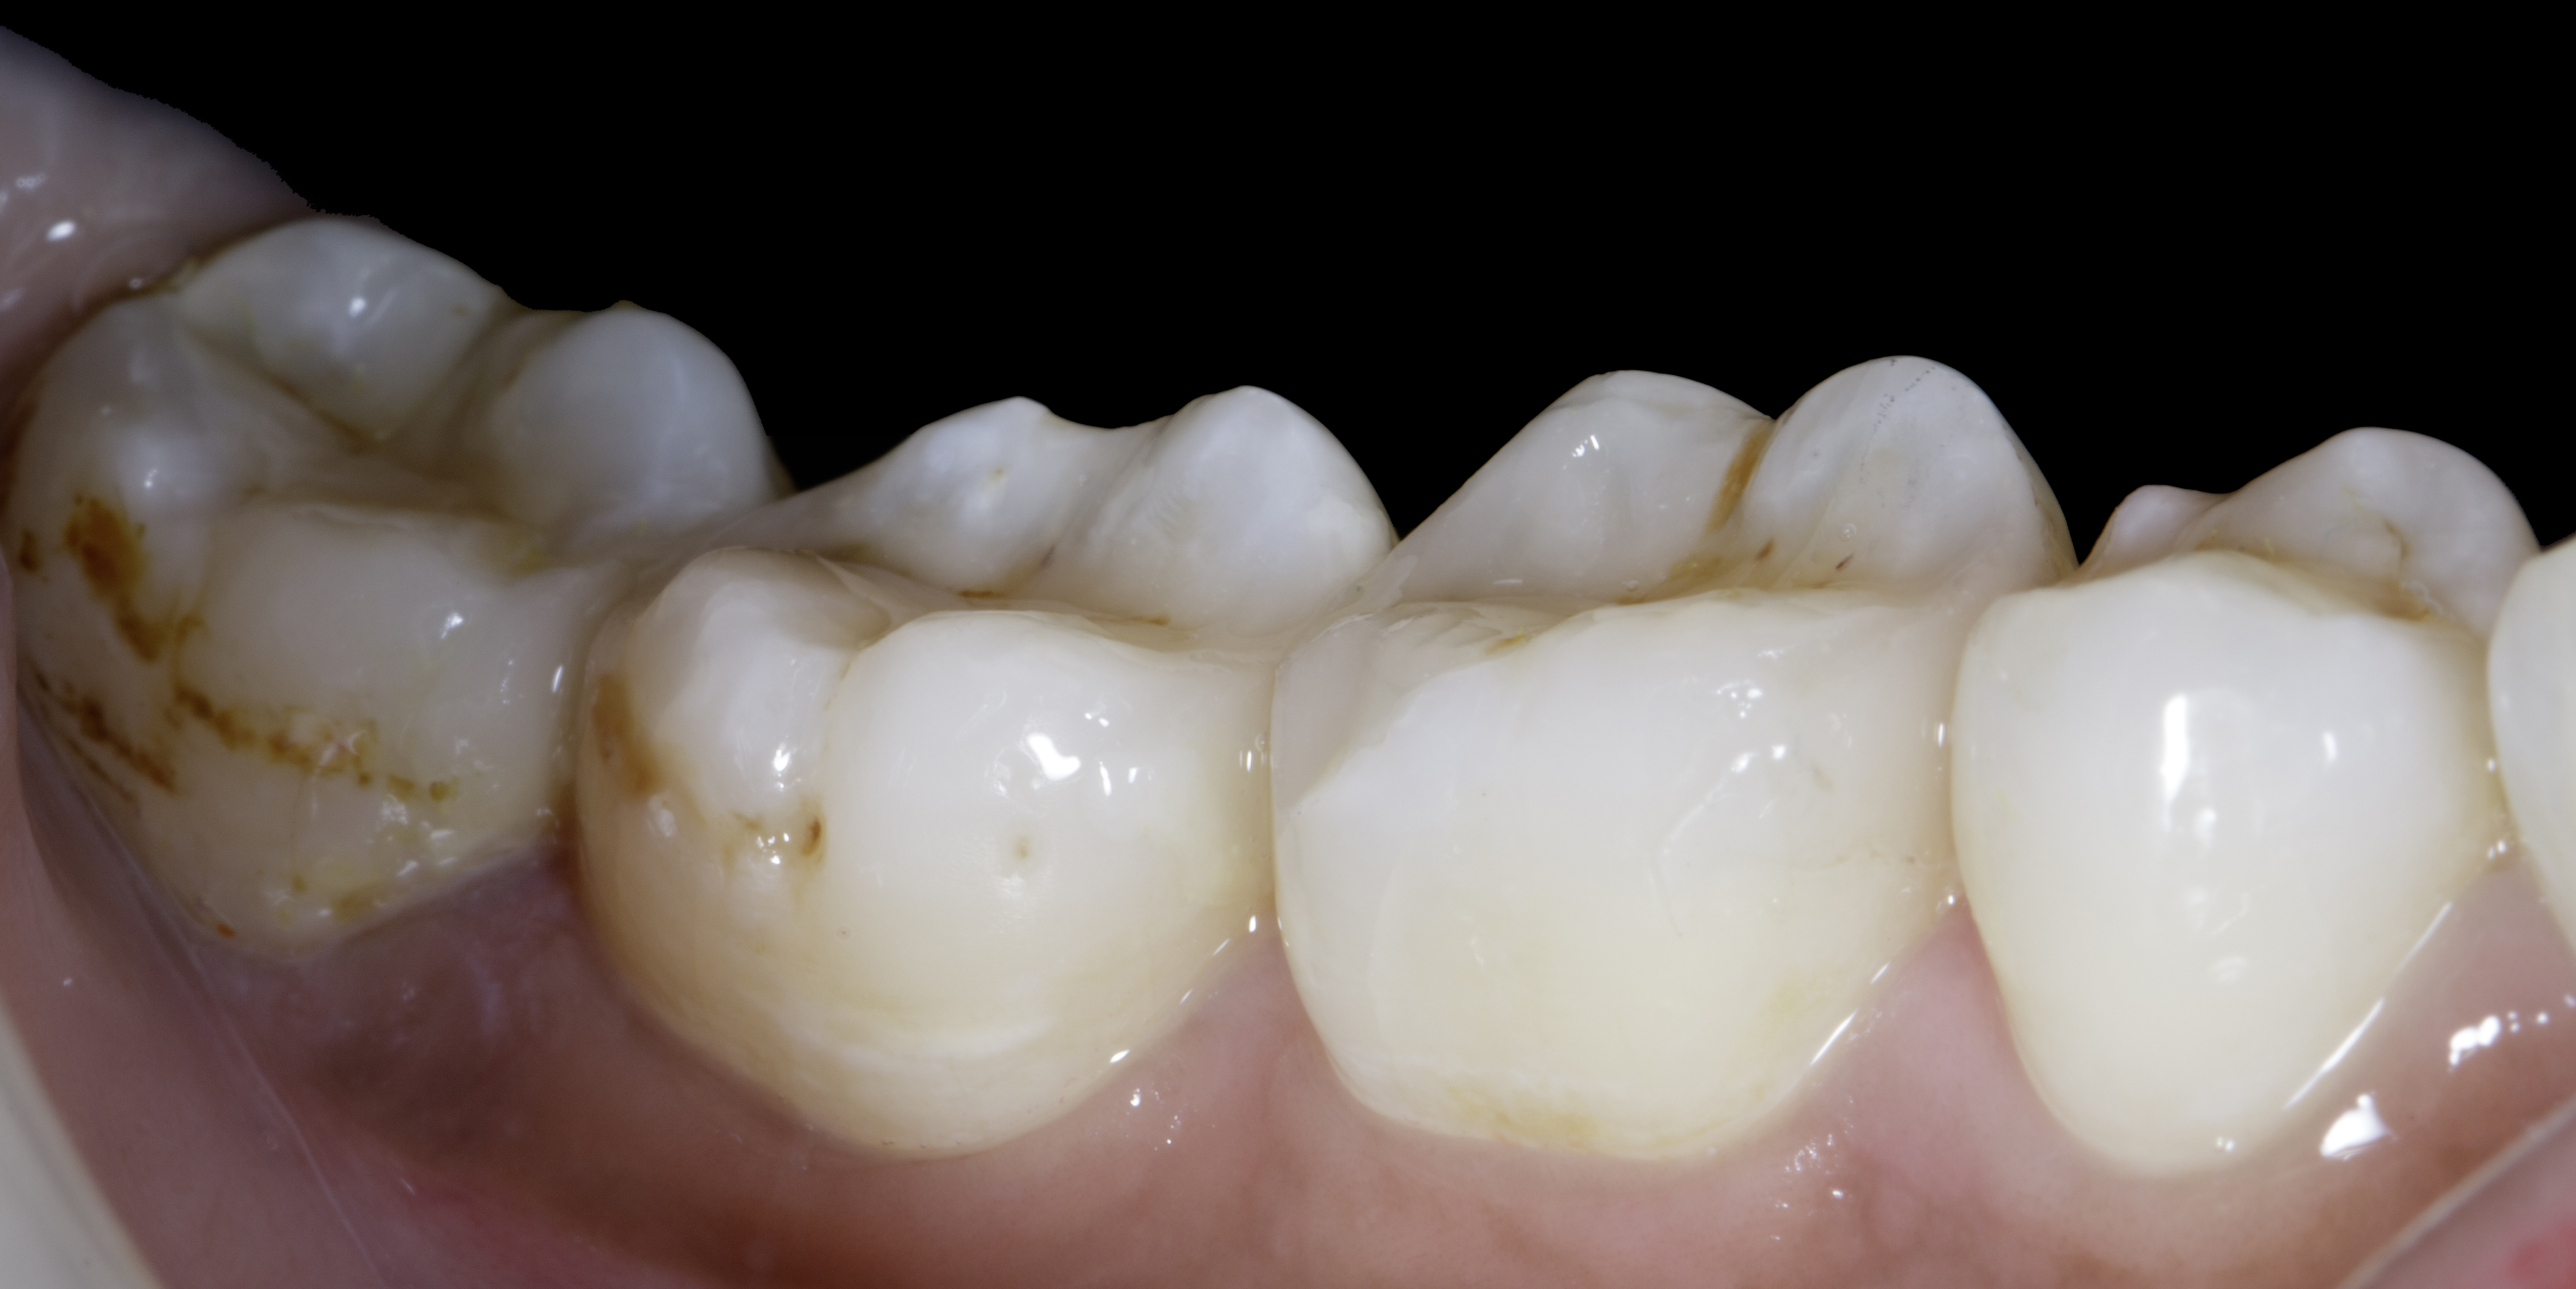

Figure 15

Figure 15. Showcasing extent large defect restored back to its natural form and function.

Figure 16

Figure 16. Buccal view - Showcasing extent large defect restored back to its natural form and function.